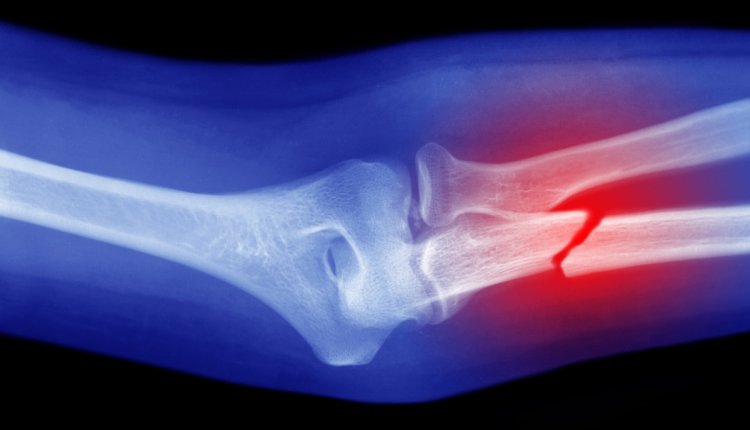

Volgens Lin Xianfeng, orthopedisch chirurg en hoofd van het onderzoeksteam, wordt de lijm in de botten aangebracht door middel van een enkele injectie, zo meldt The Global Times. De lijm met de naam 'Bone-02' lijmt dan 'de gebroken botfragmenten in slechts drie minuten aan elkaar', aldus de chirurg.

Volgens het onderzoeksteam zijn metalen platen om botten aan elkaar vast te zetten in de toekomst niet meer nodig. De lijm zou een maximale hechtkracht hebben van 180 kilo. Daarnaast kan Bone-02 volgens de onderzoekers op natuurlijke wijze door het lichaam worden opgenomen tijdens het genezingsproces van het bot. Een operatie om lijmresten te verwijderen is daardoor niet nodig.